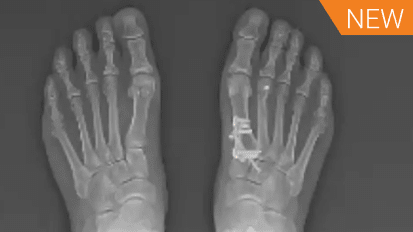

Dr. Jeremy McCormick presents his evolution of the Lapidus procedure for bunion correction, highlighting challenges with the traditional approach, recurrence, intercuneiform instability, and the role of LapiFuse™ in his practice.